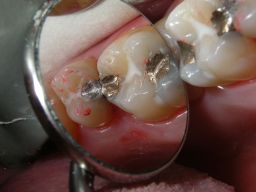

1 frische, 2 ältere Füllungen, Fissurenversiegler

Die Füllungen links wären auch in Composite gut vertretbar gewesen, die Füllungen rechts halten in Amalgam sicher länger als in Composite. Diese Amalgamfüllungen sind alle im Oberkiefer und im Alltag nicht sichtbar.

Mittelgroße und große Amalgamfüllung